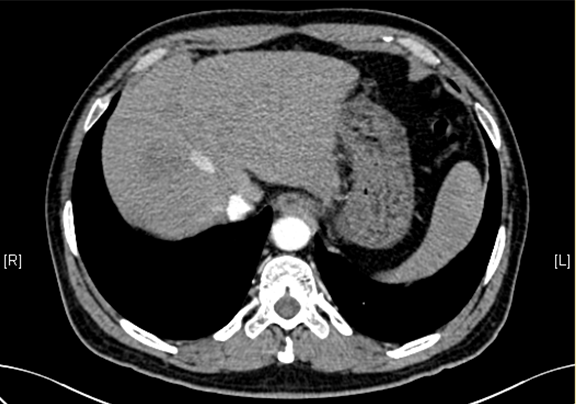

下腹部增强CT示:肝右叶恶性肿瘤可能性大;肝内多发小囊肿;肝硬化,食管胃底静脉曲张可能性大;脾脏囊肿可能性大。

将0.625mm双源薄层CT资料的静脉期和动脉期Dicom格式文件导入海信CAS系统。

通过调节窗宽窗位调整CT序号,对肿瘤,肝实质,胆囊,下腔静脉,肿瘤,肝动脉、门静脉及肝静脉等进行三维重建;系统自动计算肿瘤体积和肝脏体积。

术前CT检查:

静脉期